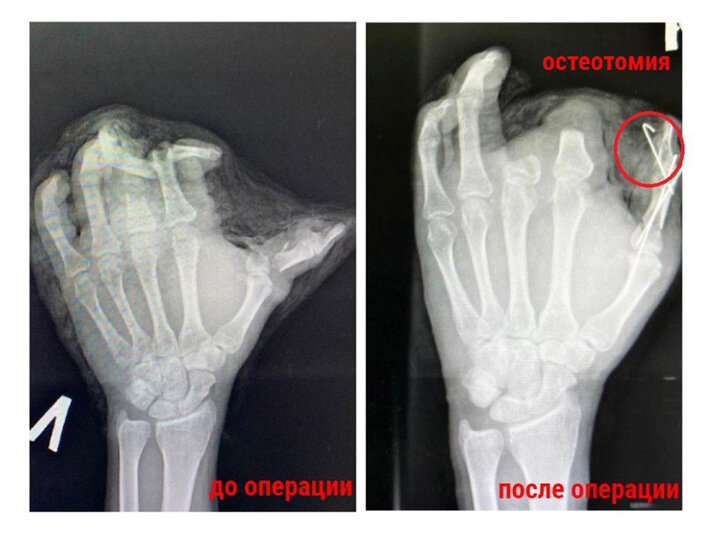

Собрать по косточкам левую кисть 38-летнего мужчины, который очень "зажигательно" встретил Новый год, удалось врачам Красногорской городской больницы. Медики, которым пришлось иметь дело с полностью раздробленной конечностью, в итоге сформировали вполне "годную руку". Как стало известно "МК", жуткую травму пострадавший получил ещё во время праздников – в его руке взорвалась петарда. Указательный и средний пальцы пациента раздробило до такой степени, что они оказались непригодны для остеосинтеза и реплантации. Специалистам ничего не оставалось, как убрать костные фрагменты и сухожилия. Зато они оставили кожные лоскуты, которыми укрыли ампутированные пальцы и сформировали эстетически приятную конечность. - На первом пальце, который в результате взрыва был раздроблен и частично ампутирован, мы провели остеотомию – собрали кость и закрепили палец спицами. Остаточный дефект кожных тканей укрыли трансплантатом – участком здоровой кожи, взятой с нижней трети предплечья», – рассказал врач-трав

Как стало известно "МК", жуткую травму пострадавший получил ещё во время праздников – в его руке взорвалась петарда. Указательный и средний пальцы пациента раздробило до такой степени, что они оказались непригодны для остеосинтеза и реплантации.

Специалистам ничего не оставалось, как убрать костные фрагменты и сухожилия. Зато они оставили кожные лоскуты, которыми укрыли ампутированные пальцы и сформировали эстетически приятную конечность.

- На первом пальце, который в результате взрыва был раздроблен и частично ампутирован, мы провели остеотомию – собрали кость и закрепили палец спицами. Остаточный дефект кожных тканей укрыли трансплантатом – участком здоровой кожи, взятой с нижней трети предплечья», – рассказал врач-травматолог-ортопед, хирург Герман Англичанинов.

На данный момент мужчина чувствует себя хорошо. Послеоперационный период прошел успешно. Лоскут и трансплантат прижился. Функциональность кисти восстановлена, а инфекционных осложнений удалось избежать.